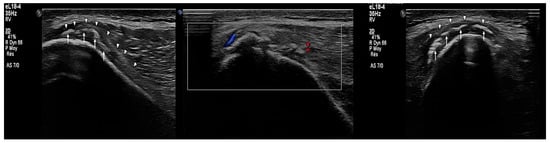

2.2. Imaging Findings

- Subperiosteal hematoma at the posterior iliac crest;

- A 20–25 mm detachment of the gluteus maximus;

- Partial involvement of the gluteus medius.